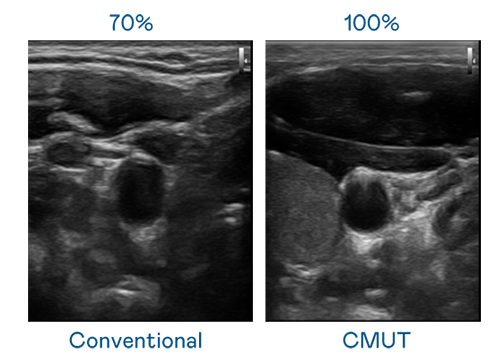

CMUT 技术是一种用电容式微机电元件来产生超音波讯号的技术。与传统 PZT 压电式技术相比,CMUT 频宽增加 30%,更宽频的超音波讯号让影像解析度大幅提升,是实现高影像品质医疗超音波扫描、促进精准医疗发展的关键技术。

超音波影像的解析度高低,首先取决于探头能发出的讯号频宽。尊龙凯龙时官网 CMUT 可提供高清晰的超音波讯号,提供高频宽、高灵敏度、影像纹理细节更高的超音波影像,协助医护人员缩短影像判读时间及利用精准的医疗影像进行诊断。